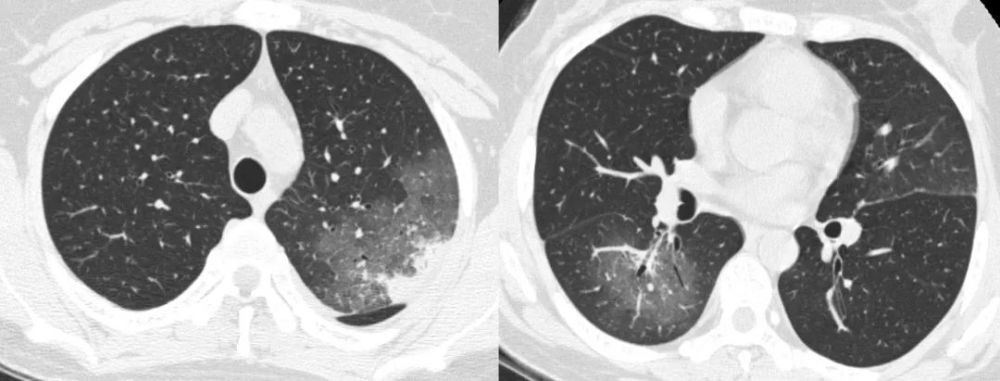

病毒性肺炎CT

间质性肺炎CT

间质性肺炎ct图片